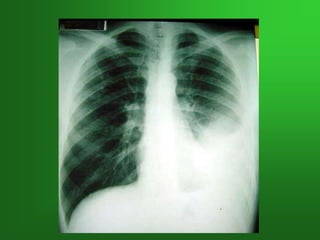

NEUMONIA LOBAR + ATELECTASIA

NEUMONIA LOBAR +ATELECTASIA